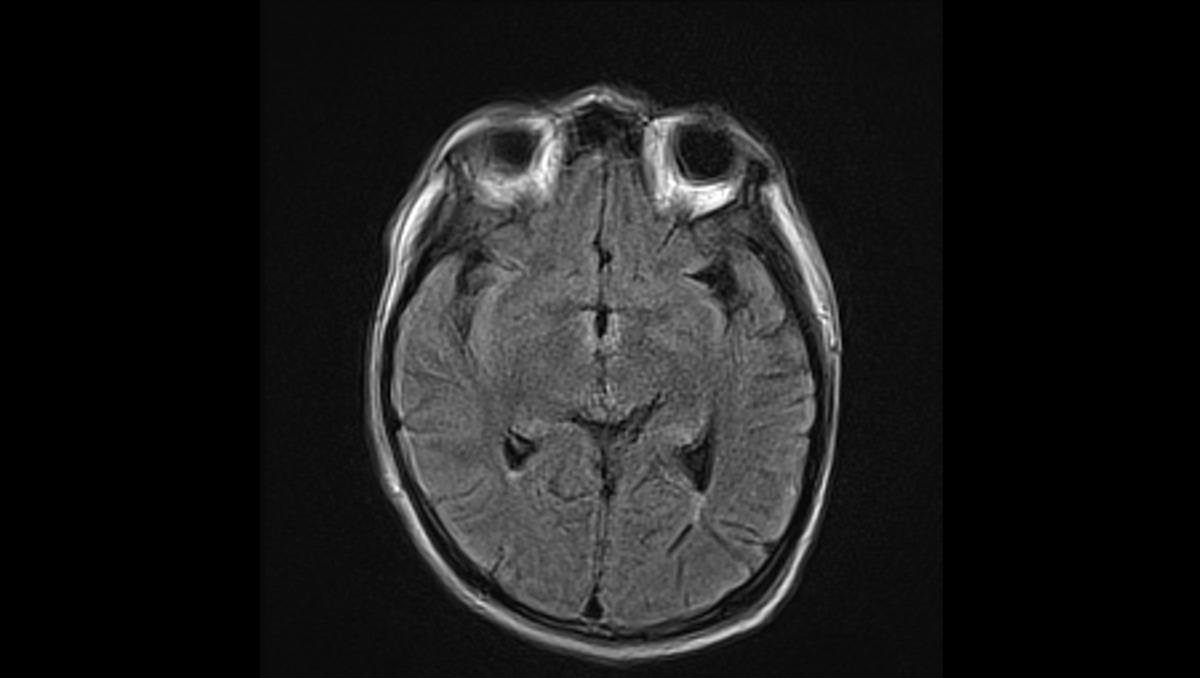

症例1:28歳男性

- 体動困難、呂律不良

- 4か月ほど前から歩行時の息切れあり、1か月前から下肢の疼痛が出現、1週間前からはベッド上で生活していた。

- 3日前から呂律が緩慢となり、増悪したため、父親が救急要請。